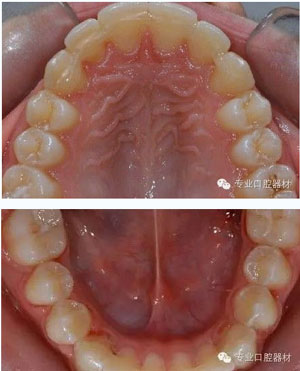

發(fā)幾張漂亮有個性的哈氏活動保持器:

其實還有一種我們也經(jīng)常采用的固定保持器,效果不錯,除了黏結(jié)有點麻煩外,其實也是不錯的選擇!